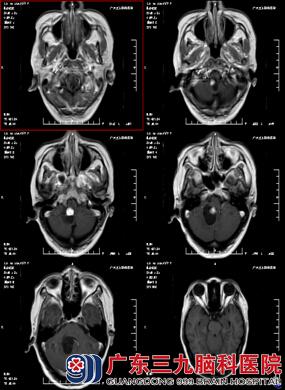

47岁的林女士,因“头痛伴呕吐20天” 到广东三九脑科医院住院治疗。林女士曾在当地医院做CT检查,提示:右侧小脑占位性病变,考虑为血管母细胞瘤。当地医院予对症处理,呕吐症状稍缓解,但头痛症状无明显缓解。现为行手术治疗来我院就诊,门诊拟“右侧小脑占位性病变”收治入院。

入院后完善术前准备后,由林涛主任主刀在全麻下行“脑干背侧血管母细胞瘤切除术”,术中见肿瘤位于脑干背侧,囊性为主,脑组织张力较高,释放囊液后,探及肿瘤,鲜红色改变,血供较丰富,大部分间隙清晰,与脑干少许粘连。术中给予镜下逐步分离并全切除肿瘤,病理提示:血管母细胞瘤(WHO I级)。手术顺利,术后给予预防感染、止血、神经营养支持、预防应激反应及全身营养支持等综合观察治疗。经10多天治疗,林女士头痛明显减轻,病情康复出院。

在外周血象常规检查中,部分患者有血红蛋白和红细胞异常增高,故检测外周血红细胞,血红蛋白对血管网织细胞瘤的诊治及预防有一定的参考价值。CT及MRI检查可明确诊断。颅后窝血管网织细胞瘤CT分型为:① 囊结型;②囊肿型;③实体型 ④脑积水型。CT平扫时呈现较均匀的低密度的结节,即瘤结节。增强扫描后瘤结节明显强化,而囊壁则无明显强化。本病应与囊性星形细胞瘤鉴别,后者囊壁多不光滑、规则,瘤结节大小不一、密度不均、边界不清,或有钙化。由MRI成像不受颅后窝骨伪影的影响,故对本病的检出率MRI高于CT,囊性病变在T1为低信号,T2为高信号,而瘤结节为等信号,Tz 为高信号,可在肿瘤周围看到 T2 相有水肿带。另外血管造影可见肿瘤结节的异常血管网或肿瘤结节染色。本病CTA典型表现为瘤结节为边缘整齐球形血管团,与1支动脉相连,动脉期可显影。